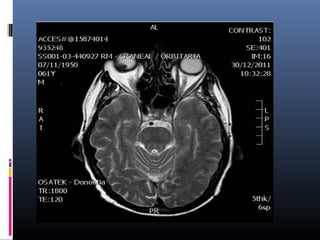

 RMN CRANEAL/ÓRBITA:

 Engrosamiento de la coroides del globo ocular derecho de

hiperintensidad en secuencia T1 y que asienta a nivel basal y

hemilateral derecho de 14 x 3 x 7 mm anteroposterior,

craneocaudal y transverso respectivamente en relación con

melanoma.

   Sin extensión extraocular ni afectación de estructuras de la

orbita.

   Sin otras captaciones patológicas en el resto del estudio.

   Globo ocular izquierdo sin alteraciones.

   Sin alteraciones parenquimatosas supra ni infratentoriales.